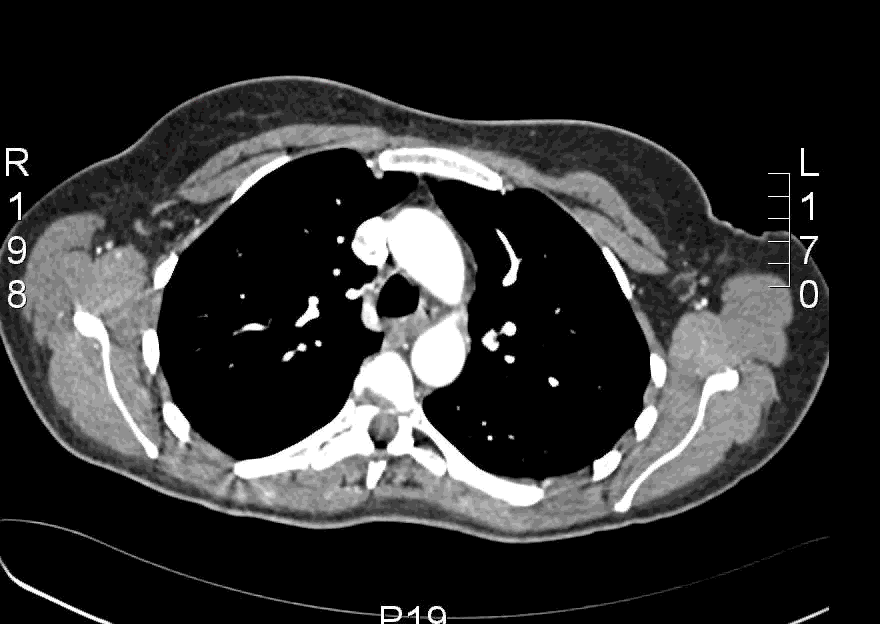

Here is an example CT scan in the axial plane:

Here is another example CT scan in the axial plane: